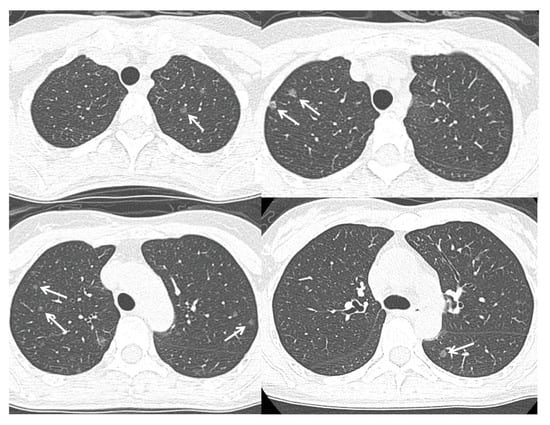

In premenopausal women, estrogens produced by their ovaries play a major role in the female reproductive organs through the ERα. In postmenopausal women, however, estrogens produced/activated by peripherally localized estrogen-metabolizing enzymes, such as aromatase, which converts androgen into estrogens, are thought to play physiologically and pathologically important roles in various organs through the ERβ, distributing systemically [77]. Estrogen can be synthesized in situ in lung cancer. Ikeda et al. measured the estrogen concentrations in the noncancerous peripheral lung tissue using liquid chromatography/electrospray tandem mass spectrometry in the postmenopausal female patients with synchronous multiple lung adenocarcinomas, and found a significantly higher level than the control cases with a single lung adenocarcinoma [78] (Figure 1). Our study of the malignant pleural effusion of lung adenocarcinoma revealed that some postmenopausal women had extraordinarily high pleural fluid estradiol concentrations, and there was no correlation between the pleural fluid concentrations of estradiol and the vascular endothelial growth factor, a marker of pleural vascular hyperpermeability [79]. In addition, the EGFR wild-type lung adenocarcinoma is probably an estrogen-dependent carcinoma, as a higher expression and potent poor prognosticator of aromatase and the ERβ in the group [62].

Figure 1.

A 48 year-old non-smoking woman was found to have multiple subcentimetre ground glass opacities (arrows) in her bilateral lungs on a low-dose CT screening. Video-assisted thoracoscopic surgery with a right upper lobe wedge resection confirmed the diagnosis of synchronous multiple lung adenocarcinomas harboring the EGFR wild-type.